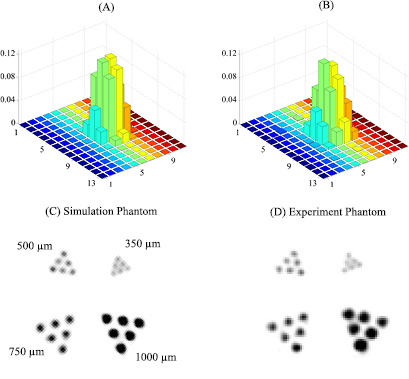

To experimentally evaluate the model, we compared the simulated pinhole response (the projection of a point source of 250 μm diameter through a given pinhole onto a CdTe detector of 2 mm thickness) to the pinhole response experimentally measured with identical geometry. In addition, we also compared the phantom images reconstructed with simulated and measured data under the same calibrated geometry. The simulated pinhole response matched reasonably well with the experimental response (figures 2A and B). On the other hand, image qualities of the experimental phantom degraded compared to the corresponding simulated results (figures 2C and D). We will discuss the potential reasons causing this degradation in section 4. Nevertheless, the simulation presented in this paper evaluated the potential performance MRC-SPECT-II could achieve.

Figure 2. A comparison between simulated and experimentally measured system responses: (A) the simulation point response function (PRF) around the FOV center of MRC-SPECT-I; (B) the corresponding experimental PRF; (C) the reconstructed image using a simulation phantom; (D) the reconstructed image using experimental data acquired using MRC-SPECT-I system. The system and phantom geometries remained the same for both the simulation study and actual experimental measurements, where MRC-SPECT-I used forty 300 μm pinholes.